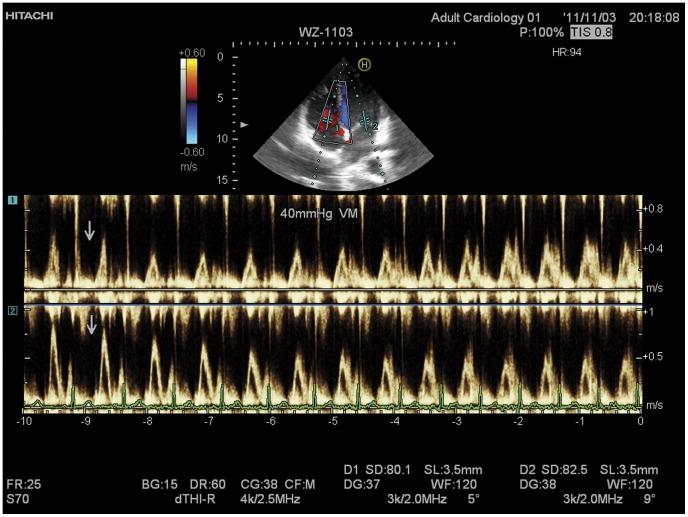

Although the influence of the Valsalva maneuver on the heart and circulatory system has been investigated, the mechanism of intrathoracic pressure influencing cardiovascular function is unclear. To test our hypothesis that the interaction between the anatomy-determined partially-intrathoracic system and the fully-intrathoracic system might explain those issues and help to disclose the mechanism, we used the Hitachi dual pulse wave Doppler echocardiographic apparatus to investigate simultaneously the beat-by-beat influence of 40-mmHg Valsalva maneuver on left and right cardiac ventricular filling in 30 male adult volunteers. The mitral and tricuspid blood inflow velocity spectra during the Valsalva maneuver were recorded simultaneously. The peak velocity (PV), velocity-time integral (VTI) and inflow volume (IV) of each cycle were measured or calculated. The PV, VTI and IV of the left heart remained unchanged at the first beat after the Valsalva maneuver onset (compared with those at rest, p>0.1) and then decreased gradually to the lowest at the 11±1.2th beat (range, 9th to 12th beat). Simultaneously, the PV, VTI and IV of the right heart decreased significantly (p<0.05) at the first cycle, decreased rapidly to the lowest at the 6±0.8th beat (range, 4th to 7th beat) and then increased gradually to the 9±1.3th beat (range, 8th to 10th beat). These results suggest that the left heart and right heart have different physiological responses to the Valsalva maneuver. These could be explained by our hypothesis, the interaction between the partially-intrathoracic system and the fully-intrathoracic system, which might help to disclose the mechanism of how intrathoracic pressure influences the heart and circulatory system.